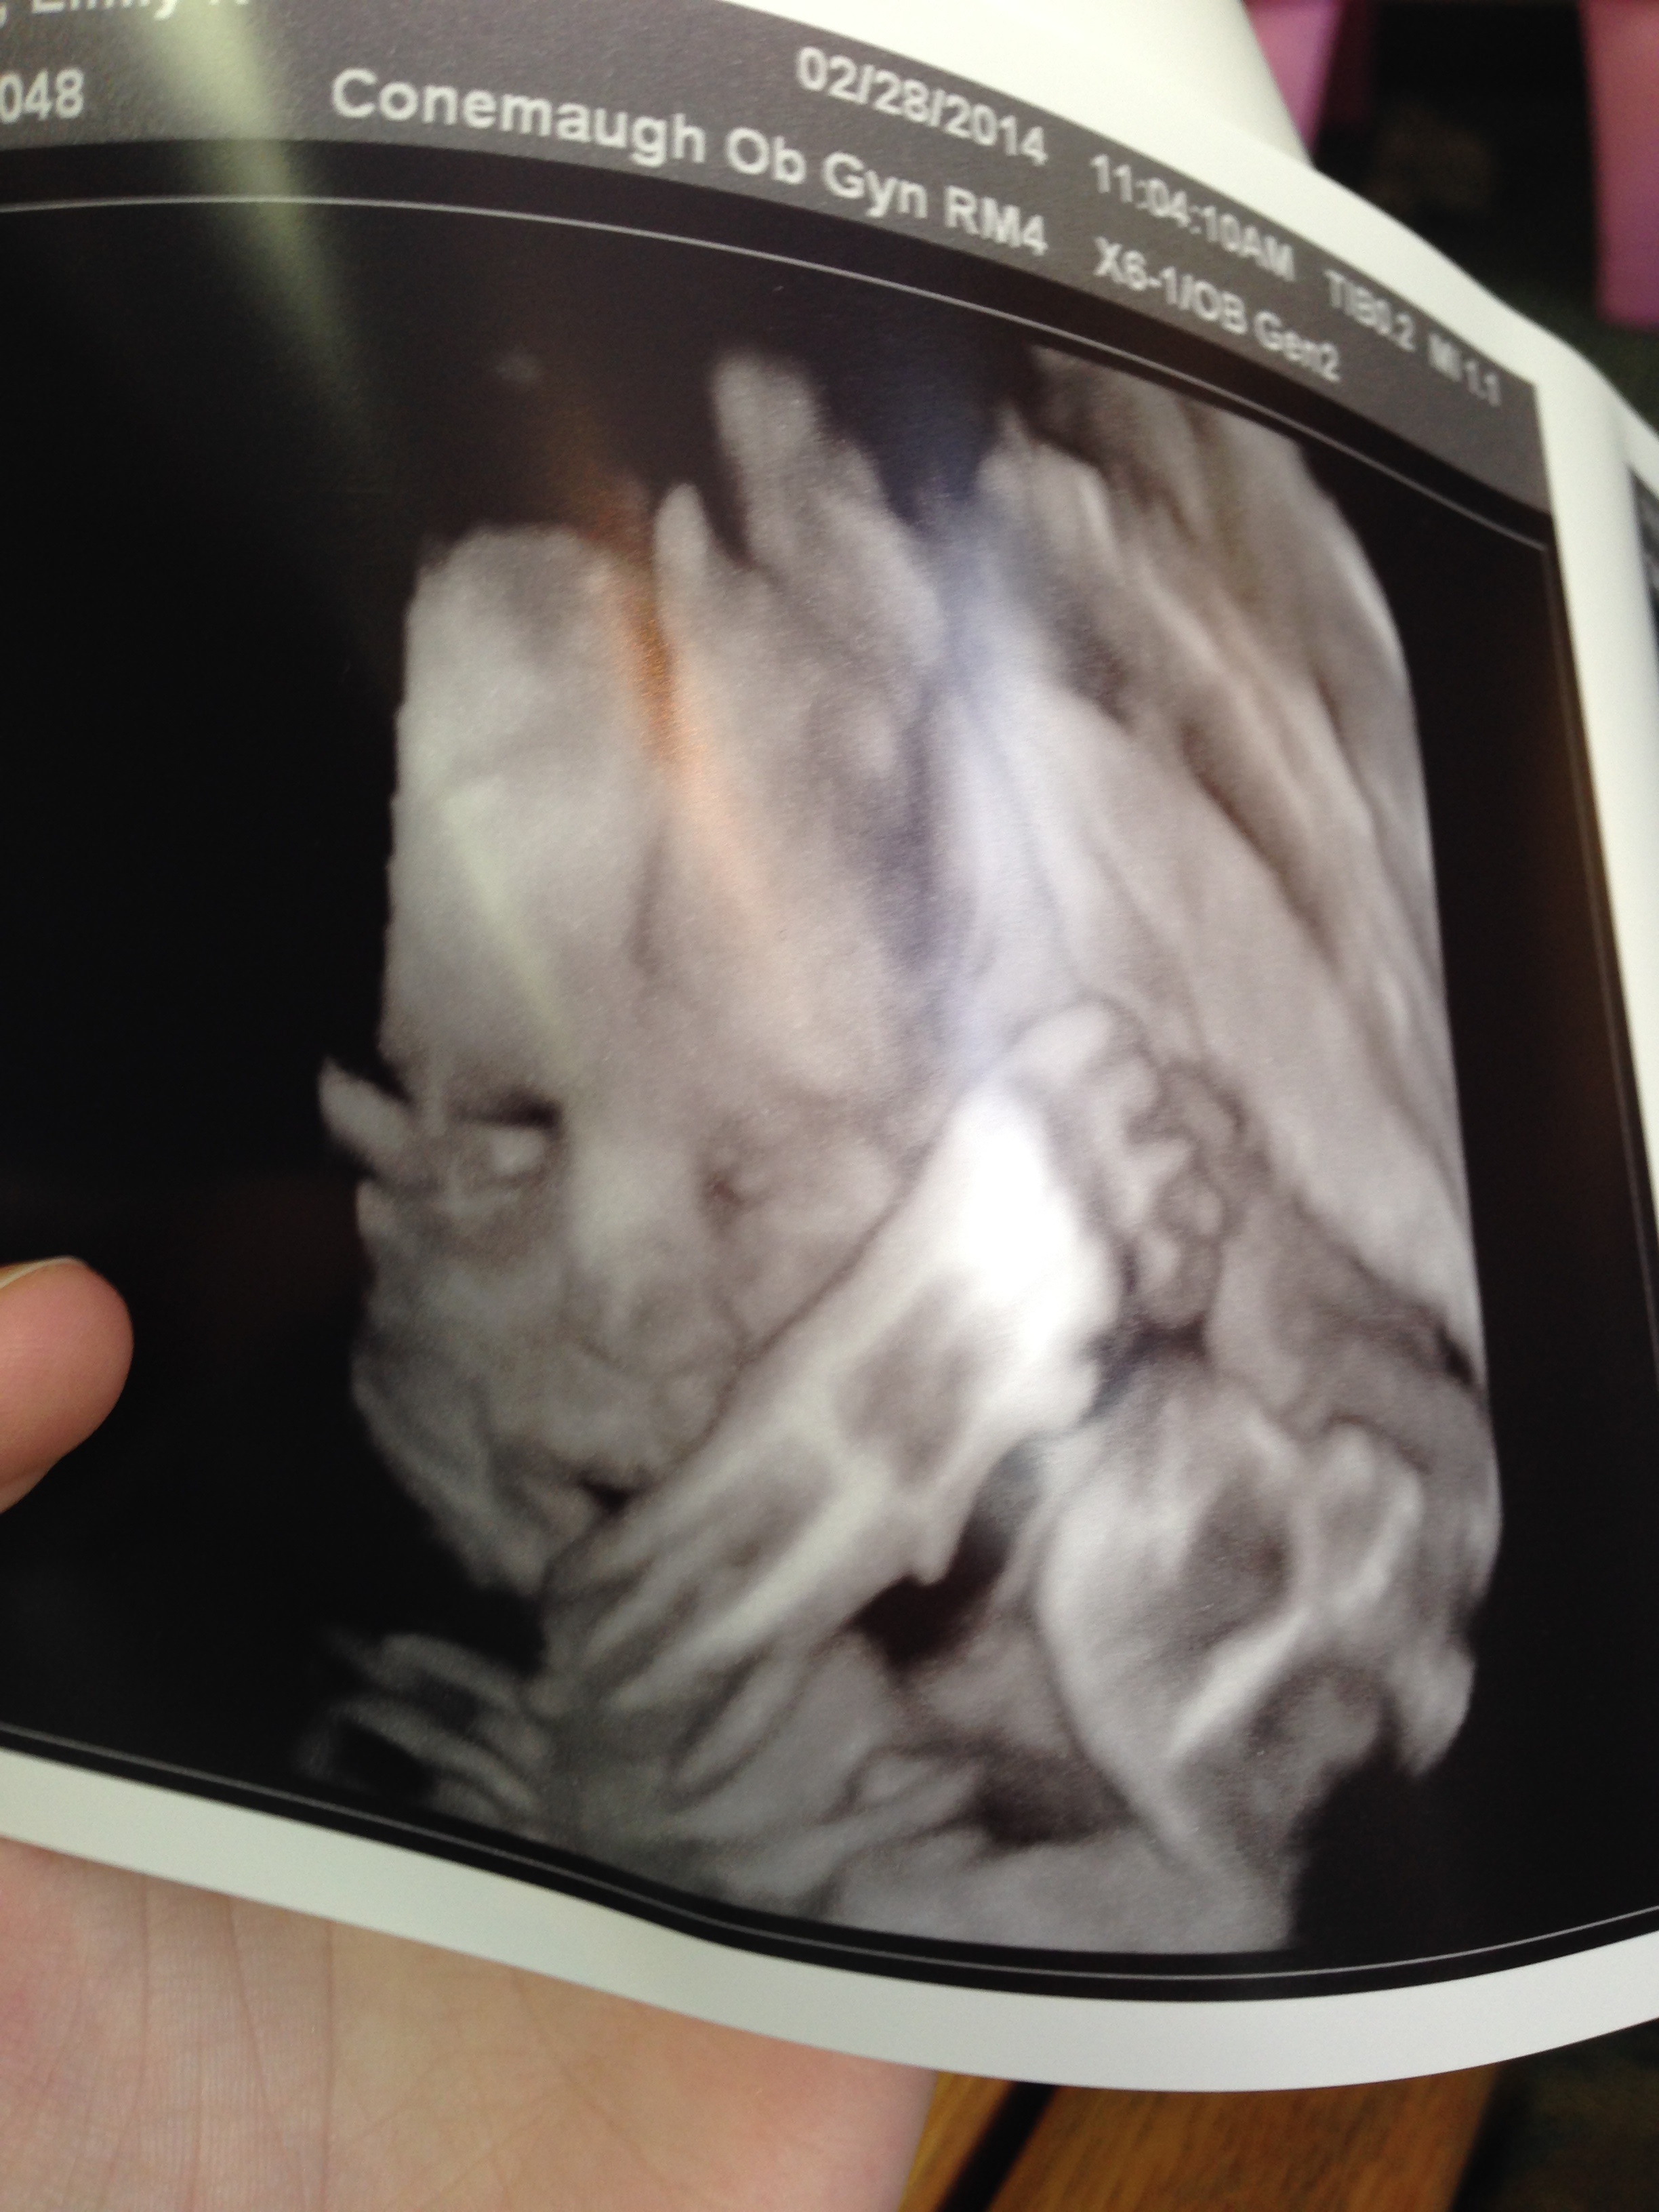

I want to thank everyone again for the kind words for my follow up ultrasound. I tried to do an update to that post, but I couldn't get it to work right. Anyway, had it this morning and the baby still has the calcium deposits or bright spots on the heart but the US tech said they are very dull, and if it were her, she wouldn't have even alerted the doctor to it in the first place (I guess they vary in brightness). His kidneys were measuring 5mm which is normal for his gestational age. This is actually up from the 4.1 and 4.2 at my A/S, but the measurements change (obviously) as baby grows bigger. All other measurements look great and he is a little big (almost 3 pounds) but nothing major. It was kind of funny because when we were looking at his profile, his nose looked HUGE. I'm not talking a little big, it looked massive. The tech could tell it had us a bit worried, so she gave us a quick view in 3D! She said they don't usually do it, so that was nice. We didn't get the best shot, but enough to see that his nose isn't freakishly big. She also said that a lot of parents think that about the nose during 3rd tri ultrasounds because the normal ultrasounds do not show soft tissue, so it appears the nose jets out more than it really is. Thanks for thinking of me and my little guy, I am so relieved and seeing the 3D shot really made it real for me! I'll try to post the 3D picture I got. It isn't as clear as some people get, but for free, I'll take it!! My husband and I joked that he looks like wolverine with his arm in front of his face